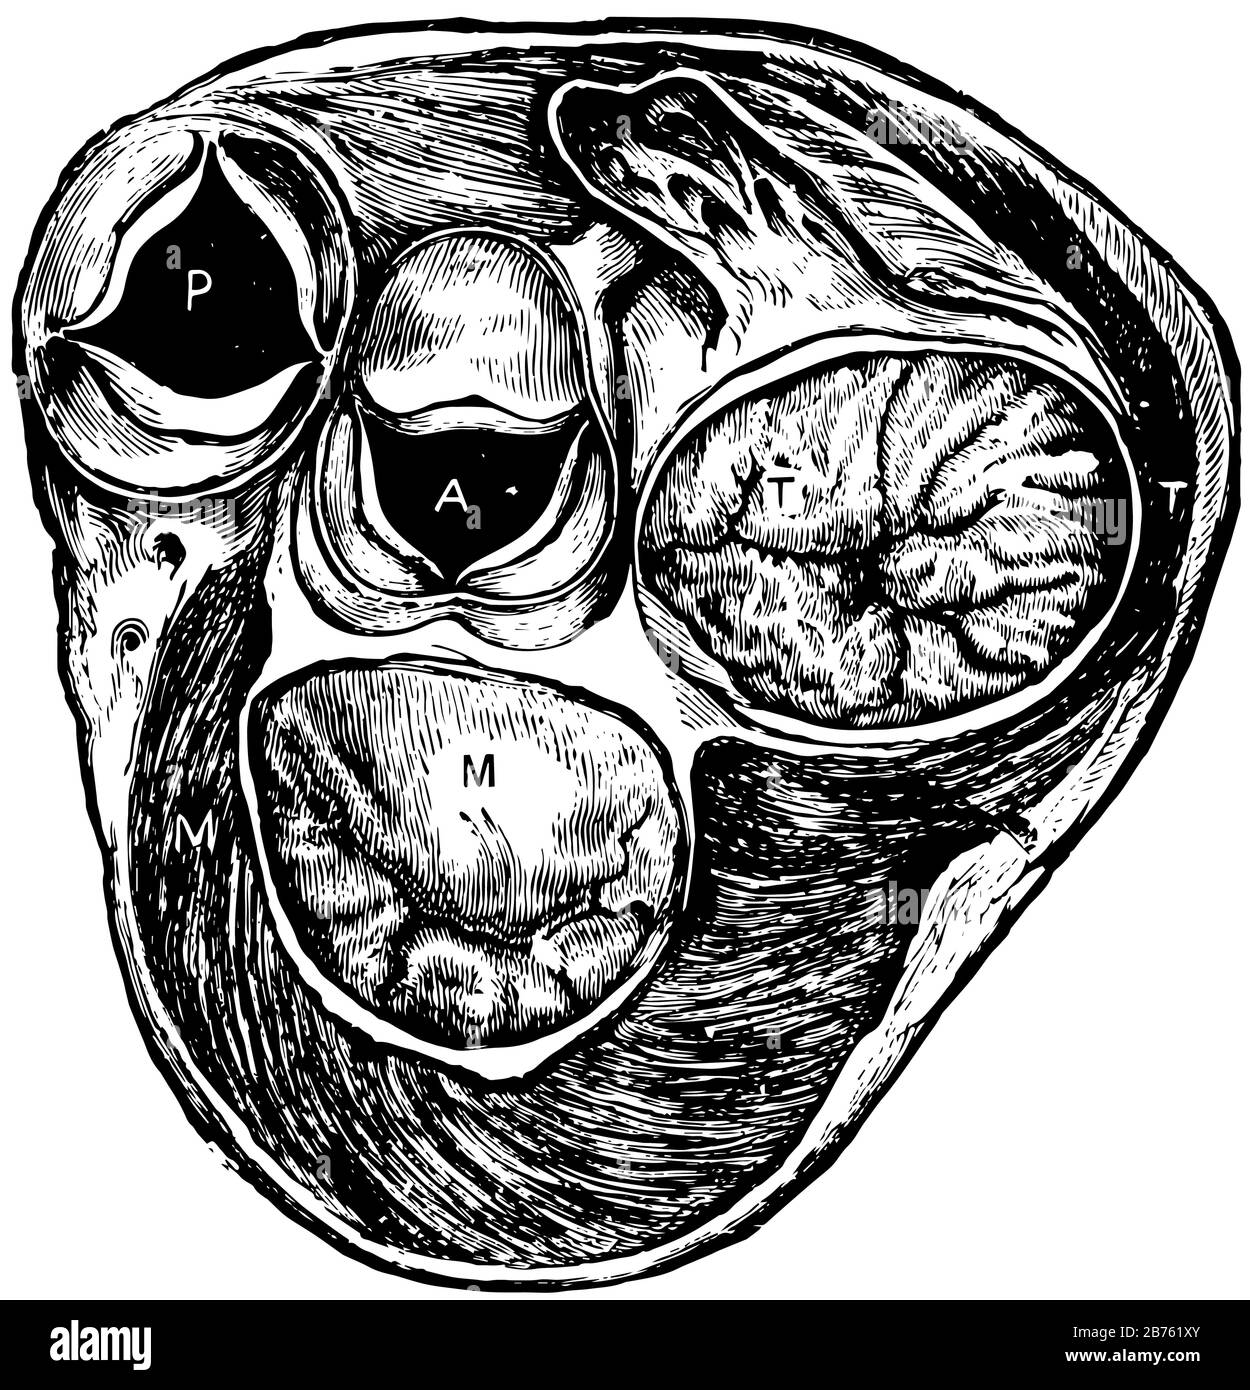

This diagram represents Section of heart at level of valves, vintage line drawing or engraving illustration. Stock Vectorhttps://www.alamy.com/image-license-details/?v=1https://www.alamy.com/this-diagram-represents-section-of-heart-at-level-of-valves-vintage-line-drawing-or-engraving-illustration-image348643203.html

This diagram represents Section of heart at level of valves, vintage line drawing or engraving illustration. Stock Vectorhttps://www.alamy.com/image-license-details/?v=1https://www.alamy.com/this-diagram-represents-section-of-heart-at-level-of-valves-vintage-line-drawing-or-engraving-illustration-image348643203.htmlRF2B761XY–This diagram represents Section of heart at level of valves, vintage line drawing or engraving illustration.